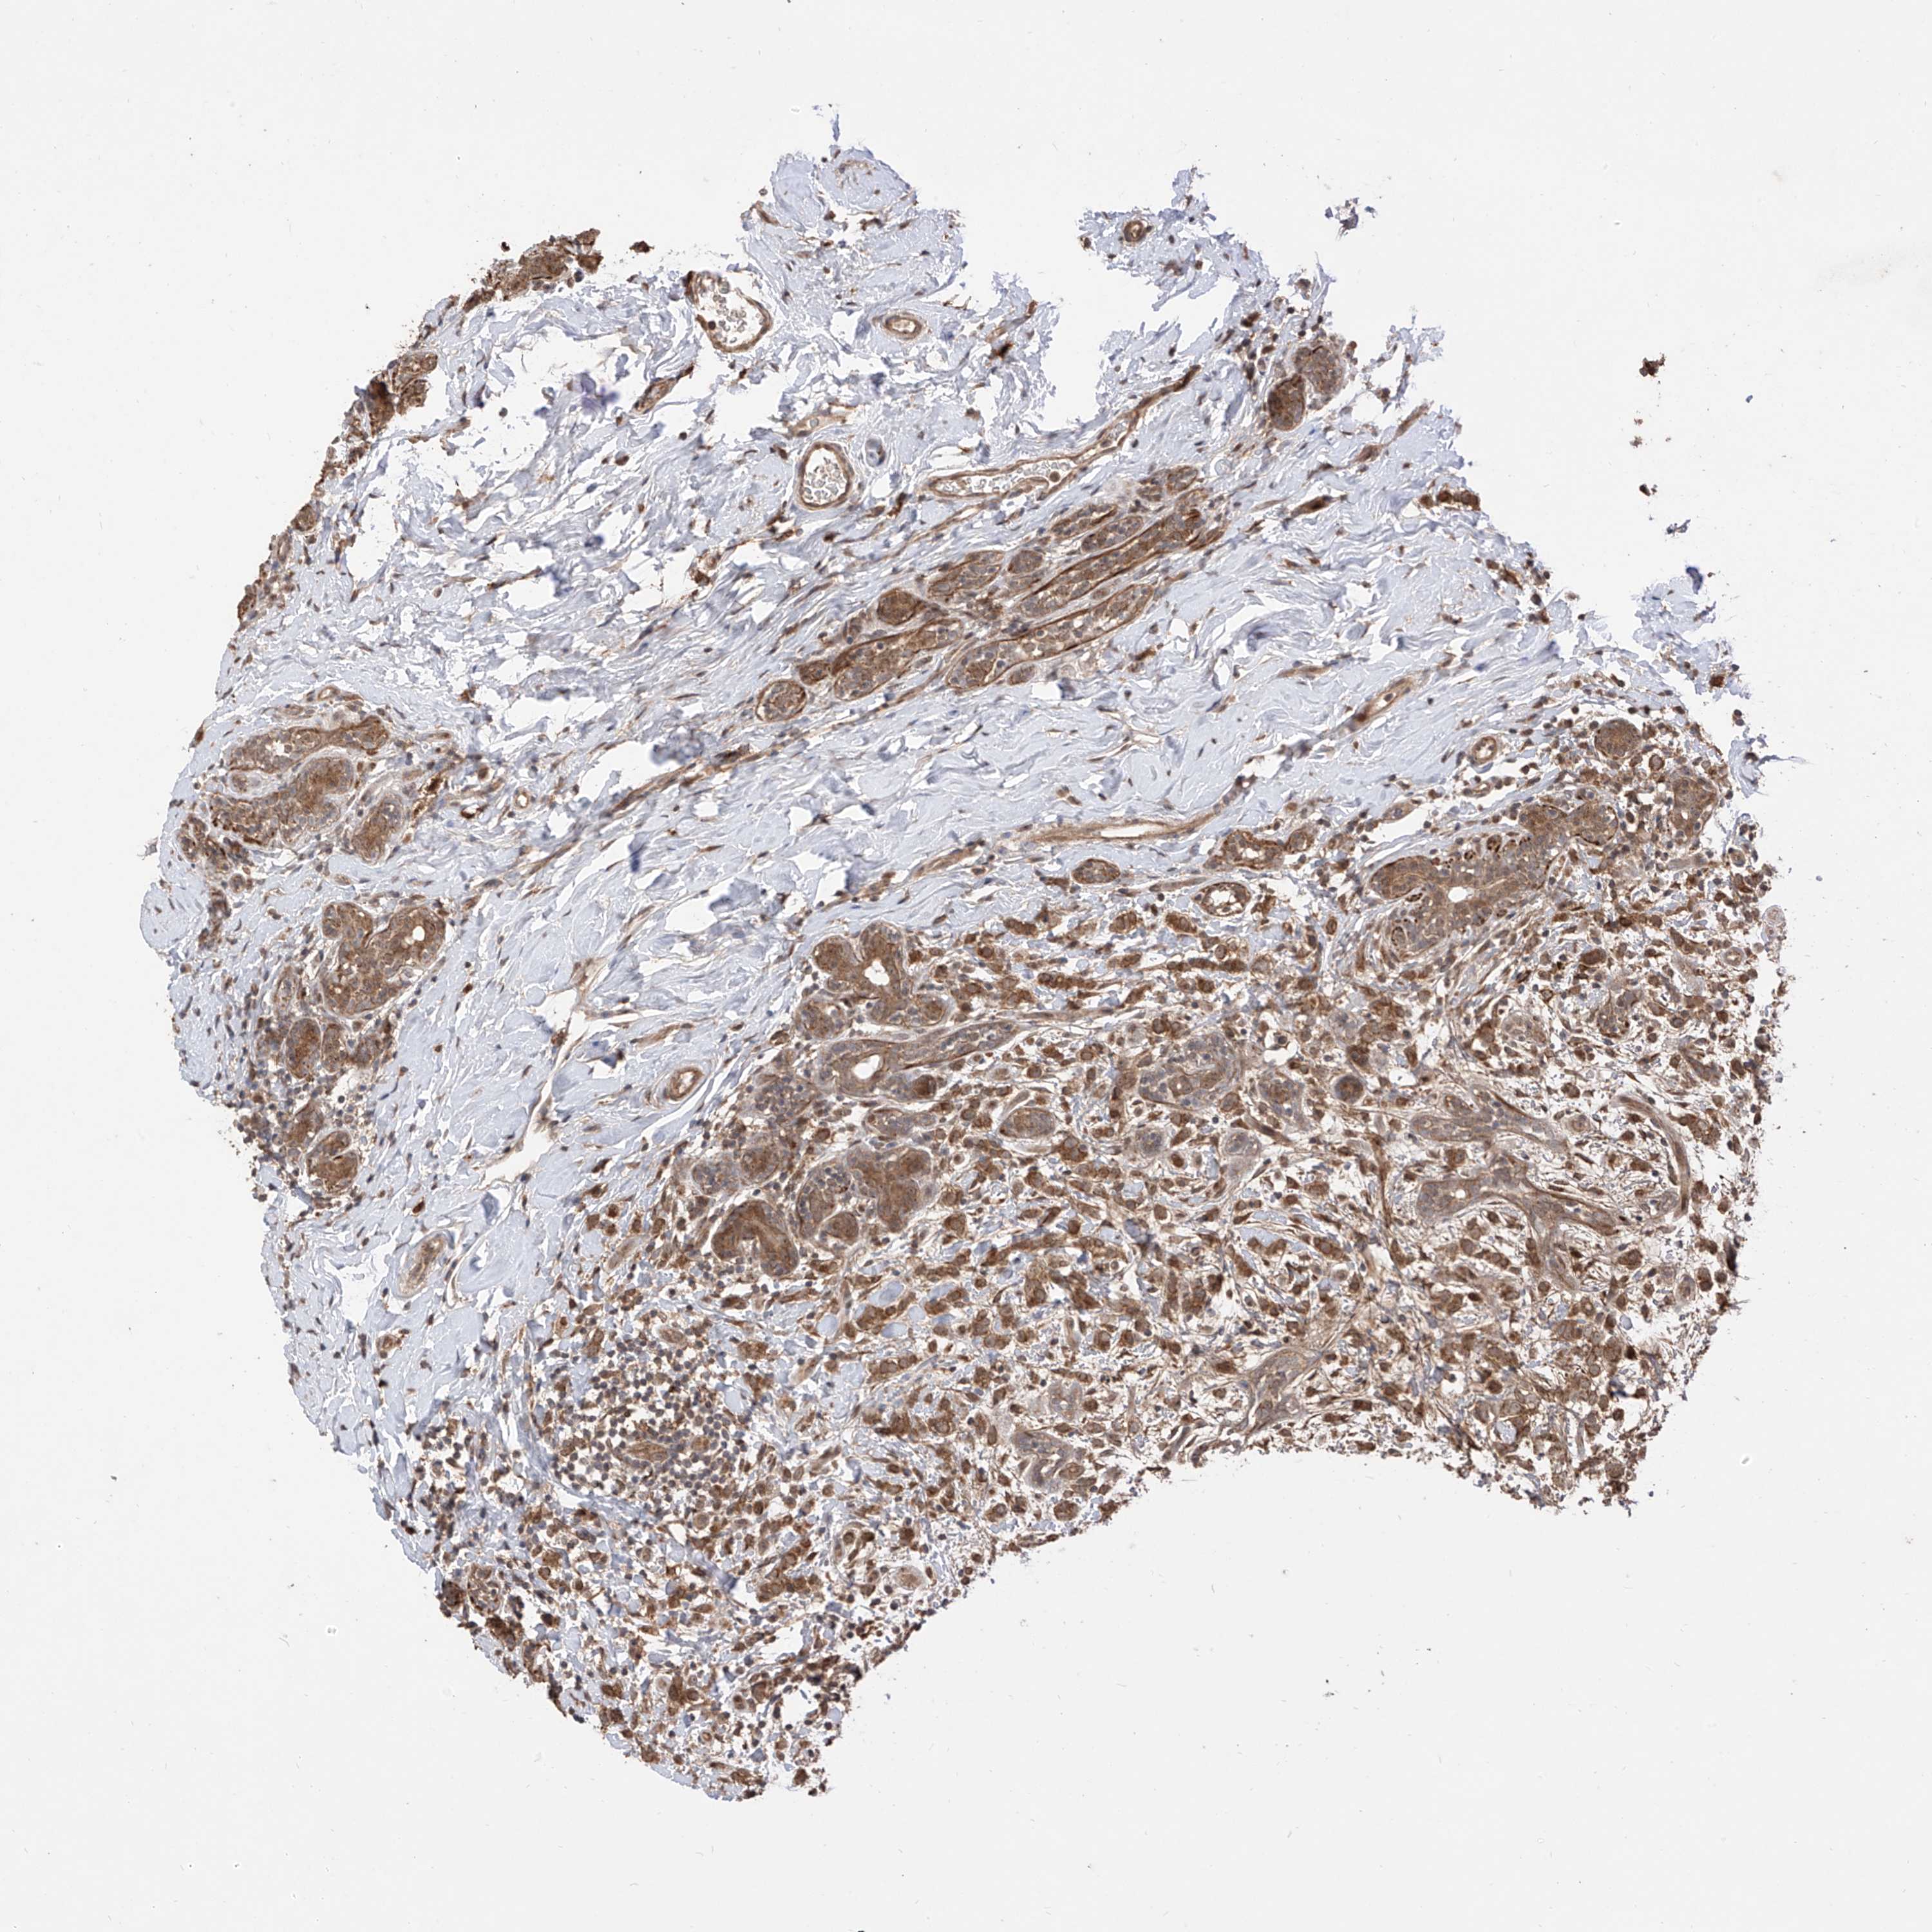

CANCER BREAST CANCER Show tissue menu

BRCA TCGA BRCA VALIDATION PROTEIN EXPRESSION